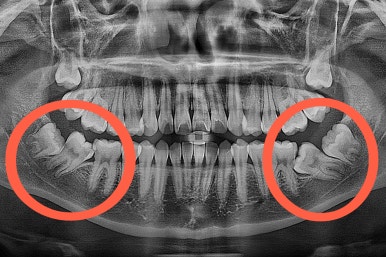

부산교정 키다리아저씨치과에 처음 내원하셨을 당시의 입안 모습과 X-ray 사진입니다.

키다리 : 어금니가 양쪽 다 굉장히 쓰러져 있어서 현재로서는 제대로 치료할 방법이 없습니다.

키다리 : 사랑니는 더 뒤에 또 묻혀있고, 입 안에 쓰러진채로 보이는 치아는 평생 써야 할 어금니에요.

맨 안쪽 치아가 마치 사랑니인 것처럼 누워있고 애매하게 나와있었어요.

문제는 해당 치아가 썩었다는건데 기울어 있는 치아를 제대로 치료할 방법은 사실상 없죠. 앞에 치아에 가려진 부분이 썩었으니깐요.

저대로 계속 놔두게 되면 누워있는 어금니 + 앞쪽 어금니 두 개가 다 상해서 결국 뽑아야 되는 상황까지 벌어질 수 있어요. 그것도 양쪽으로 모두 다 요.